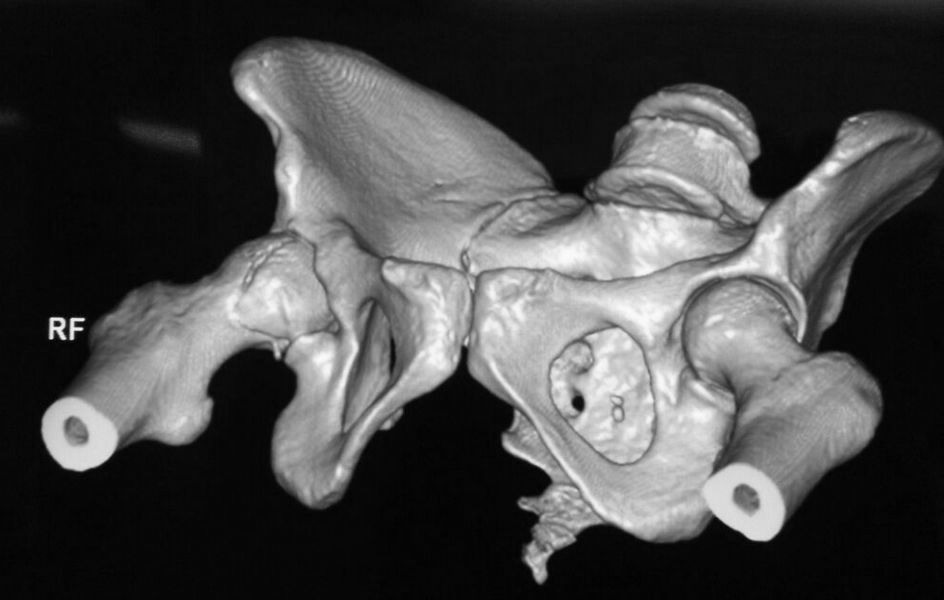

правой нижней конечности в день поступления. КТ контроль показал довольно

сносную картину результата репозиции. Отломок головки оставался в полости

сустава во время вывиха, т.к. видимо сохранилось прикрепление со связкой.

На КТ остается широкой суставная щель, что косвенно может указывать на

интерпозицию мягкими тканями, либо "встать на место" мешает медиальный

отломок головки.

Тактика остается прежней: после стабилизации состояния пациентки выполнить

задний доступ по Kocher-Langenbeck с флип-остеотомией большого вертела и

задним вывихом головки бедра. Остеосинтез головки винтами. Ревизия полости

сустава и далее по ситуации.